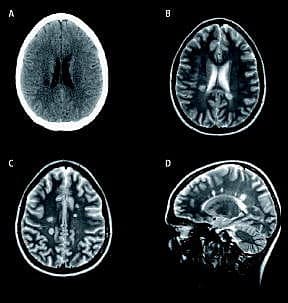

Computertomografi (CT) af cerebrum viste to hypodense områder omkring 1 cm store i højresidig corona radiata og centrum semiovale uden opladning efter kontrastindgift ( A ). Efterfølgende magnetisk resonans (MR)-skanning viste på T2-vægtet optagelse hyperintense, ovoide forandringer op til 1 cm store i hvid substans periventrikulært ( Dawson fingers ) og i corpus callosum med opladning i en enkelt forandring efter kontrastindgift ( B + C + D ). Forandring-erne blev tolket som en akut, demyeliniserende lidelse suspekt for multipel sklerose (MS) [1]. Spinalvæsken viste let forhøjet immunglobulin G-indeks, men fravær af oligoklonale bånd, hvilket er foreneligt med en autoimmun reaktion, der disponerer for udvikling af MS.

Sensitivitet for påvisning af plaques i cerebrum ved MR-skanning og CT er henholdsvis 95% og 38%, hvor alle CT-påviste plaques også ses med MR [2]. Efter initial CT, der ofte er udført i den helt akutte fase, er MR førstevalg ved billeddiagnostisk udredning og opfølgning af patienter med demyeliniserende forandringer og formodet eller verificeret MS.

Ved CT-påviste hypodense forandringer i hvid substans og relevante resultater af klinisk undersøgelse hos især yngre patienter, skal MS overvejes som diffentialdiagnose, og supplerende MR-skanning tilrådes.